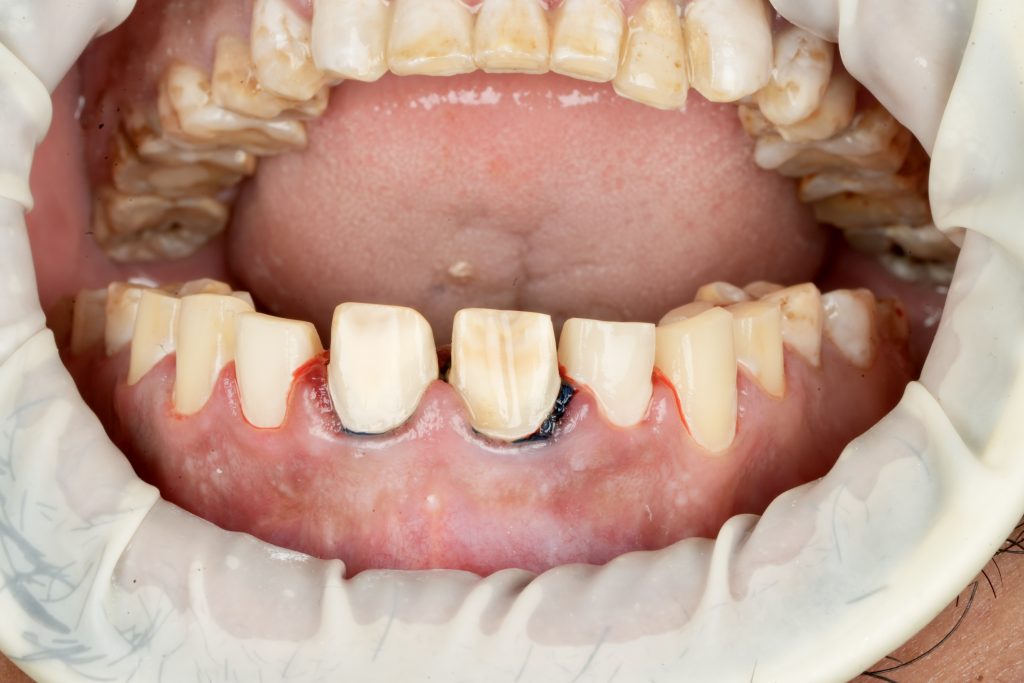

Using silicone indexes derived from the mock-up, controlled minimal-thickness veneer preparations (0.3–0.5 mm) were carried out under microscope magnification to ensure uniform reduction and margin clarity (Fig 2). Finish lines were placed juxta-gingivally with soft-tissue protection using Teflon and double-cord isolation.